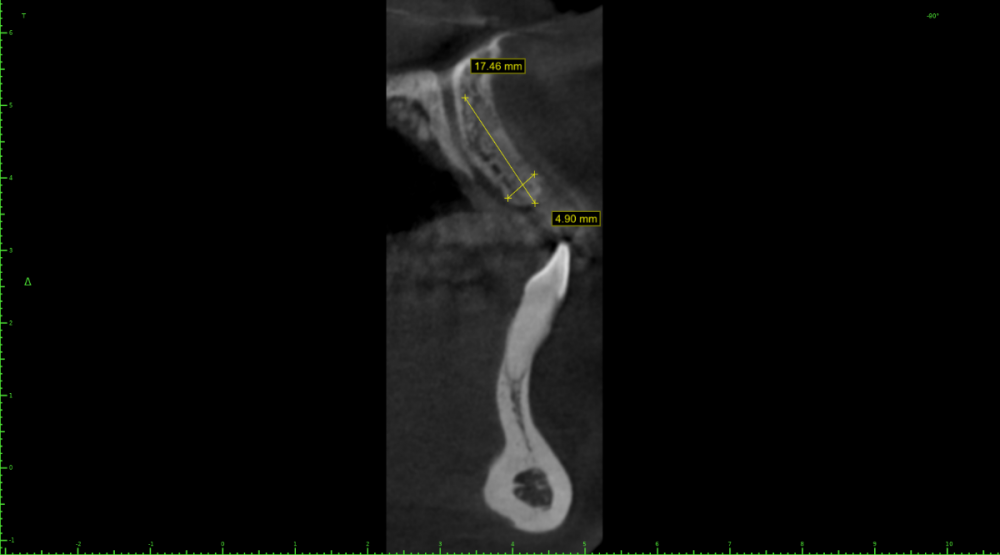

Женька Опубликовано 6 февраля, 2022 Поделиться Опубликовано 6 февраля, 2022 Как это решить максимально просто? Ни НКР ни расщепления ранее не делал (нормальную НКР, с пинами, ауто+ксено и тд). Так что вариант "что получается лучше" не подходит. Какие ещё срезы нужны для планирования? Пациентка маленькая, худощавого телосложения. На данный момент ходит с "бабочкой". Сам склоняюсь к НКР, тк это в моей голове проще реализуемо. Может есть какие-то другие варианты? Ссылка на комментарий

Irouil Опубликовано 6 февраля, 2022 Поделиться Опубликовано 6 февраля, 2022 Анкилос 3.5 с андерпрепом и небольшой компрессией, заглубить Ссылка на комментарий

Irouil Опубликовано 6 февраля, 2022 Поделиться Опубликовано 6 февраля, 2022 (изменено) 25 минут назад, Женька сказал: @Irouil в наличии только Дентиумы (ну возможно ещё мис получится заставить начальника закупить) Дентиум 3.6 по такому же принципу 25 минут назад, Женька сказал: но всех ведь не будешь протоколить?) Всех будешь Изменено 6 февраля, 2022 пользователем Irouil Ссылка на комментарий

Женька Опубликовано 7 февраля, 2022 Автор Поделиться Опубликовано 7 февраля, 2022 @TIGER ну как при моделировании шаблона, да? @Irouil получается типа расширение гребня имплантатом, вы об этом? и более нёбное позиционирование Ссылка на комментарий

Irouil Опубликовано 7 февраля, 2022 Поделиться Опубликовано 7 февраля, 2022 2 часа назад, Женька сказал: получается типа расширение гребня имплантатом, вы об этом? и более нёбное позиционирование Пилотное сверло 2.0 + спредер 2/3, к примеру Ссылка на комментарий

pit Опубликовано 8 февраля, 2022 Поделиться Опубликовано 8 февраля, 2022 (изменено) 06.02.2022 в 22:25, Женька сказал: 4 часа назад, Doctor Vlad сказал: 06.02.2022 в 22:25, Женька сказал: @pit увы, фоток улыбки нет, как и воспоминаний... (надо как-то иначе видимо строить первичную консультацию, но всех ведь не будешь протоколить?) тем не менее какие варианты при высокой и низкой? При низкой линии улыбки узкий имплант в небную позицию и все( если не хочется заморачиваться) При высокой тоже в более небную позицию+ растянуть кость (винтовыми остеотомами например) + ССТ+ временная коронка Изменено 8 февраля, 2022 пользователем pit Ссылка на комментарий